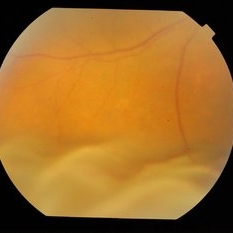

RE fundus of a 65-year-old male with bilateral uveitis. Speckled appearance of fundus with inferior exudative RD. Other features and FFA suggestive of VKH disease.

Photographer: Mallika Goyal, MD, Apollo Health City, Hyderabad